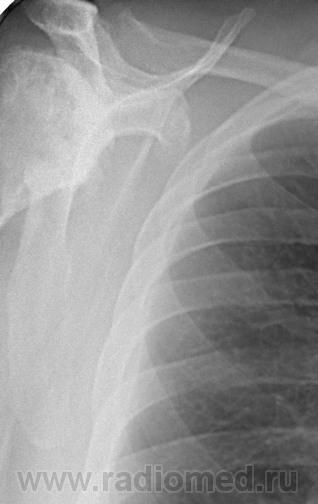

Снимки плечевых суставов.

Foto010.jpgFoto011.jpgFoto012.jpgFoto013.jpg

Уважаемый Александр, приходиться признать, что на цифровой рентгенограмме легких изменения плечевых суставов видны лучше, чем на "обрезаных" и недоэкспонированых снимках суставов. По имеющимся данным могу только сказать, что деф. артроз с кистовидной перестройкой структуры есть. Под хрящевой опухолью (возможно - хондросаркома) левой лопатки я имела в виду тень, отмеченую красными стрелками, которая в поле снимка не вошла. Моя вина - в силу специфики работы такие узкоформатные снимки давно были вредными, т.к. очень часто патология остается за пределами снимка. Остается рекомендовать рентгенография левой лопатки в прямой передне-задней и косой проекциях, а лучше - КТ...